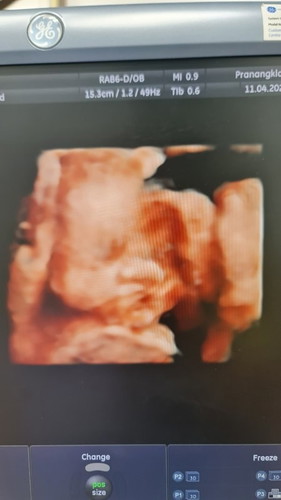

อยากรู้ว่าน้องมีภาวะปากแหว่งไหม ภาพบอกอะไรได้บ้างค่ะแม่ๆ

ความจริงถ้ามีอะไรผิดปกติหมอจะเป็นคนบอกเองนะคะ หมอไม่ได้บอกอะไรแม่หรอคะ